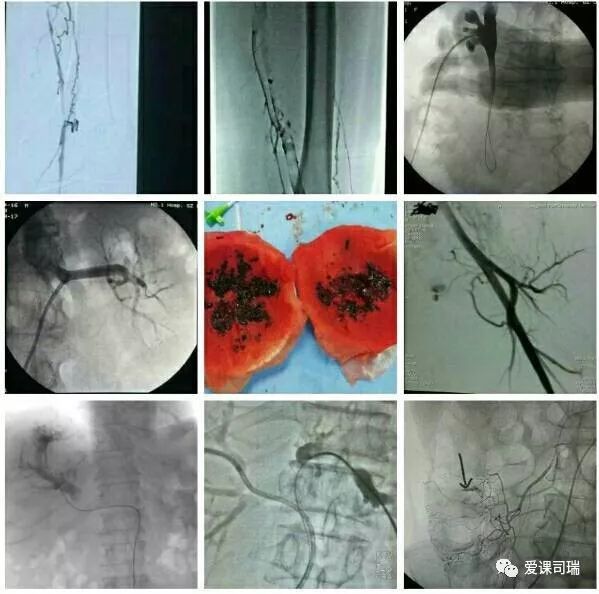

1.有影像设备的引导:在能够“看穿身体”的影像设备帮助下,不需要切开人体,就能看到体内脏器和病变,实现“可视化”。

3.诊断与治疗相融合:介入医生能够通过影像设备直接看到病变,疾病的诊断就很容易明确,随即又可立刻转入治疗过程,实现“诊断治疗一体化”或“诊治一条龙”。整个过程都看得见,治疗过程中又可继续诊断,如果判断效果还没有达到预期,立即追加治疗也非常方便。

总的说来,如果吃药效果不佳,又不能或不愿开刀的病,都可能通过介入方法得到解决。比如动脉、静脉、尿路、胆道等处堵塞,咯血、便血、尿血、呕血,糖尿病下肢冰凉,甚至是顽固性高血压等等,介入医生用针和细小的导管等器材,无须开刀,也许就能顺利解决,见效往往还很快。如果有这些情况,不妨找介入医生看看。

概括地说,介入诊疗有以下优势: 1.可以远道施术:借助于导管等器材,可以从对病人最有利、远离病变的部位入手,将治疗器材送达病变局部,再施行精细的治疗。比如,头部有病,我们可以方便地从大腿跟部进管,经血管插管到头部去,从而避免直接切割或穿刺头部。 2.创伤轻微,容易耐受:借助于影像设备这“第三只眼睛”的引导,无须开刀即能清晰显示病变部位,从而进行准确的治疗操作。 3.可重复性强:由于创伤小,不会造成局部的粘连和组织缺损,因而可以多次反复地进行治疗,直到病变完全康复为止。 4.定位准确:有影像设备作实时的引导和监控,没有视觉盲区,因而可以“指哪打哪”。 5.疗效高、见效快:对很多病变可以起到“立竿见影”的效果。 6.并发症发生率低:也就是说安全性高,由上述多种优势的综合作用所致。 7.方便联合应用多种介入技术:介入诊疗技术种类繁多,各有特色和优势,可以方便地联合应用,取长补短,从而进一步增强治疗效果。

“介入”的应用范围涵盖了头颈、胸腹、四肢等各个部位,涉及神经、心血管、呼吸、消化、泌尿生殖、骨关节等各个系统器官的病变诊治。

介入放射学按诊治目的可分为介入诊断学和介入治疗学,按涉及学科可分为神经介入、心血管介入、肿瘤介入、妇产科介入等学科分支;介入诊疗技术按进入途径则可分为血管性和非血管性两大类介入技术。